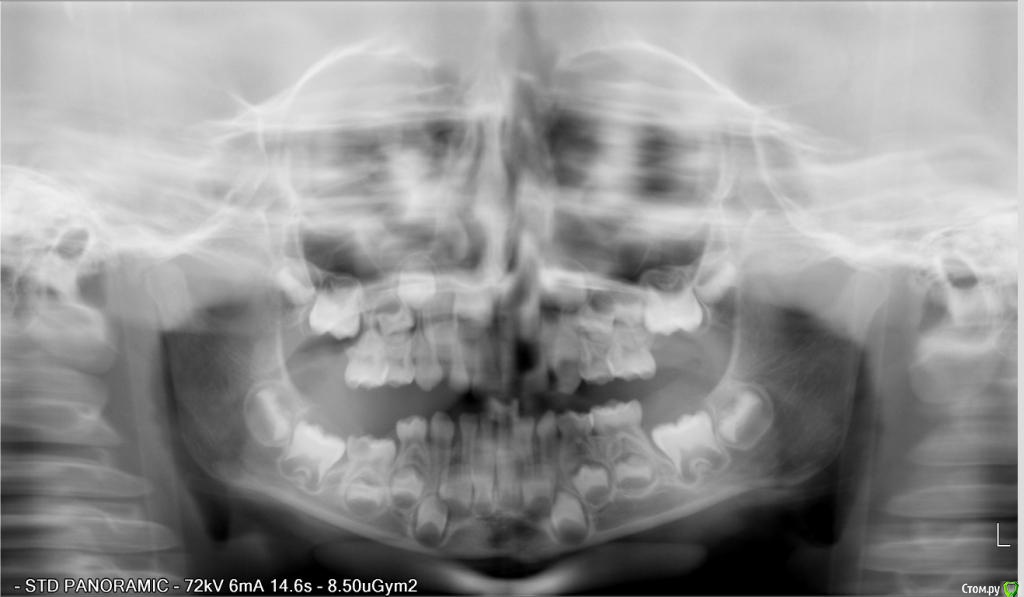

Анкилоз. Наклонен зуб. Нетипичный детский случай.

Консультация  по поводу ребенка. Девочка, 2011 года рождения.

С лета 2014 г. начал прорезываться нижний правый зуб 5-ка. До настоящего времени зуб находится по своей высоте в десне. Так как этот зуб по площади своей поверхности находился на 30-40% под десной, то начал появляться кариес. Ребенку было три года и вычищать досконально было очень тяжело. Заметив темное пятно, обратились к терапевту. Нам без снимка сказали, что это пульпит и тому подобное. Кроме того, с тех пор ребенок отказался посещать врача – испугалась. Грубое обращение. Впоследствии образовалась полость. Кариес. Обратились к другому терапевту, который поставил диагноз «пульпит». Сделали снимок, который показал анкилоз. Ортодонт и терапевт сомневались в лечении зуба, предлагая его удалить. Ортодонт высказывала опасения, что удаление тоже опасно, так как прямо под корнями этого зуба расположен постоянный зуб. Говорила, что зуб уже никогда не прорежется. Терапевт предлагала попробовать спасти зуб. Убрать нависающую часть десны и пролечить пульпит, поставить пломбу.

По снимку сказали нет зачатков каких-то постоянных зубов. Это наследственное по моей линии. Глубокий прикус, в дальнейшем требуется ортодонтическое лечение

Результат: зуб не прорезался, но пульпит вылечен, поставлена пломба.

Через год начал прорезываться зуб, стоящий рядом с пролеченным. Прорезался и… наклонился. Теперь он ушел в наклон с одной стороны, закрывая при этом часть поверхности 5-ки. Наплыла десна, но не критично. С одной стороны зуб полностью вырос, с другой – в десне.

Прилагаю снимки. Один до того, как прорезался наклоненный зуб. Второй - после его прорезывания и лечения зуба с анкилозом. Прошу прощения за качества некоторых снимков.

Пломба на снимках имеет розовый, почти красный цвет.